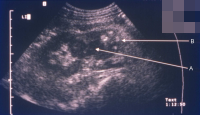

Diagnostisch spielen Sonographie und Computertomographie die entscheidende Rolle: Zumeist fallen die Veränderungen als diffuse Raumforderung auf (Abbildung 20).

Beim Fehlen einer entzündlichen Symptomatik wird differentialdiagnostisch nicht selten sonographisch die Diagnose Tumorverdacht gestellt.

Beispielhaft die bildgebende Diagnostik und das Organpräparat bei einem Patienten mit XGP (Abbildung 21). Hier führte das intraoperative Schnellschnittergebnis Tumor zur Nephrektomie.